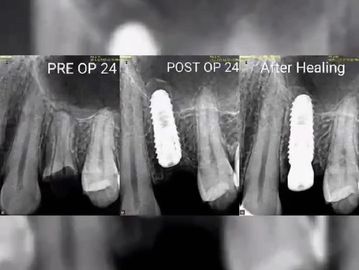

Discover a permanent solution for replacing missing teeth with high-quality dental implants. This treatment not only restores chewing function and comfort but also ensures a natural appearance. Prior to the procedure, a detailed dental consultation is essential to evaluate your specific needs. Additionally, our practice offers services in children's dentistry, crowns and bridges, and root canal treatment to provide comprehensive care.